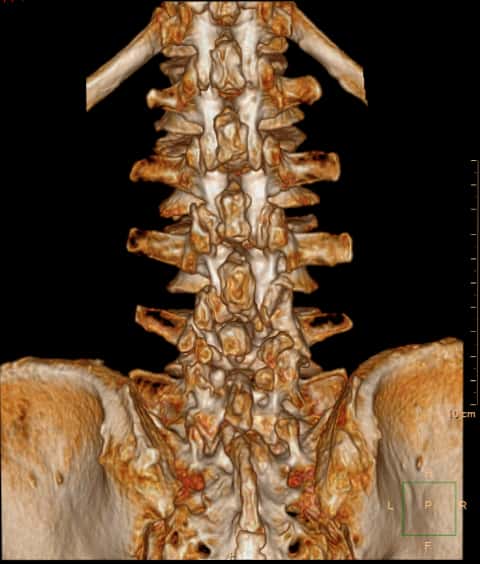

腰4/5水平,小关节及关节后方有大量的增生

腰4/5水平,小关节及关节后方有大量的增生。

多个腰椎小关节及关节后方有大量的增生。

断面可见明显的增生改变,提示腰椎不稳定。